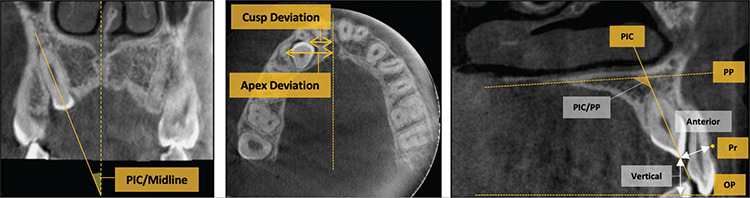

A thorough clinical and radiographical assessment of an impacted maxillary canine's location forms the basis for proper diagnosis and successful treatment outcomes. Implementing a correct biomechanical approach for directing force application primarily relies on its precise localization. Poor biomechanical planning can resorb the roots of adjacent teeth and result in poor periodontal outcomes of the canine that has been disimpacted. Furthermore, treatment success and time strongly rely on an accurate assessment of the severity of impaction, which depends on its 3D spatial location. The evolution of cone-beam computed tomography (CBCT) radiographs provides more detailed information regarding the location of the impacted canines. In addition, the literature has shown that CBCT imaging has enhanced the quality of diagnosis and treatment planning by obtaining a more precise localization of impacted canines. This review article highlights current evidence regarding comprehensive evaluation of three-dimensional orientations of impacted canines on CBCT images for precise diagnosis and treatment planning.